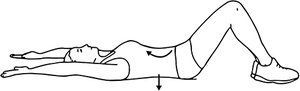

Abdominal hollowing is best described as drawing the navel in and up toward the diaphragm. The objective is to strengthen the transverse abdominus (TA) and intrinsic core muscles. It is commonly performed while lying on a pressure gauge as a biofeedback device to ensure adequate TA contraction.

Abdominal hollowing is another core stabilization tool that follows a progression, just as any other stabilization exercise. For example, in the supine position, a common progression would be:

- Knees bent (hook-lying)